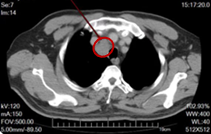

图2.基线及治疗期间复查CT

图3.维持治疗3周期后右上气管旁新发淋巴结转移